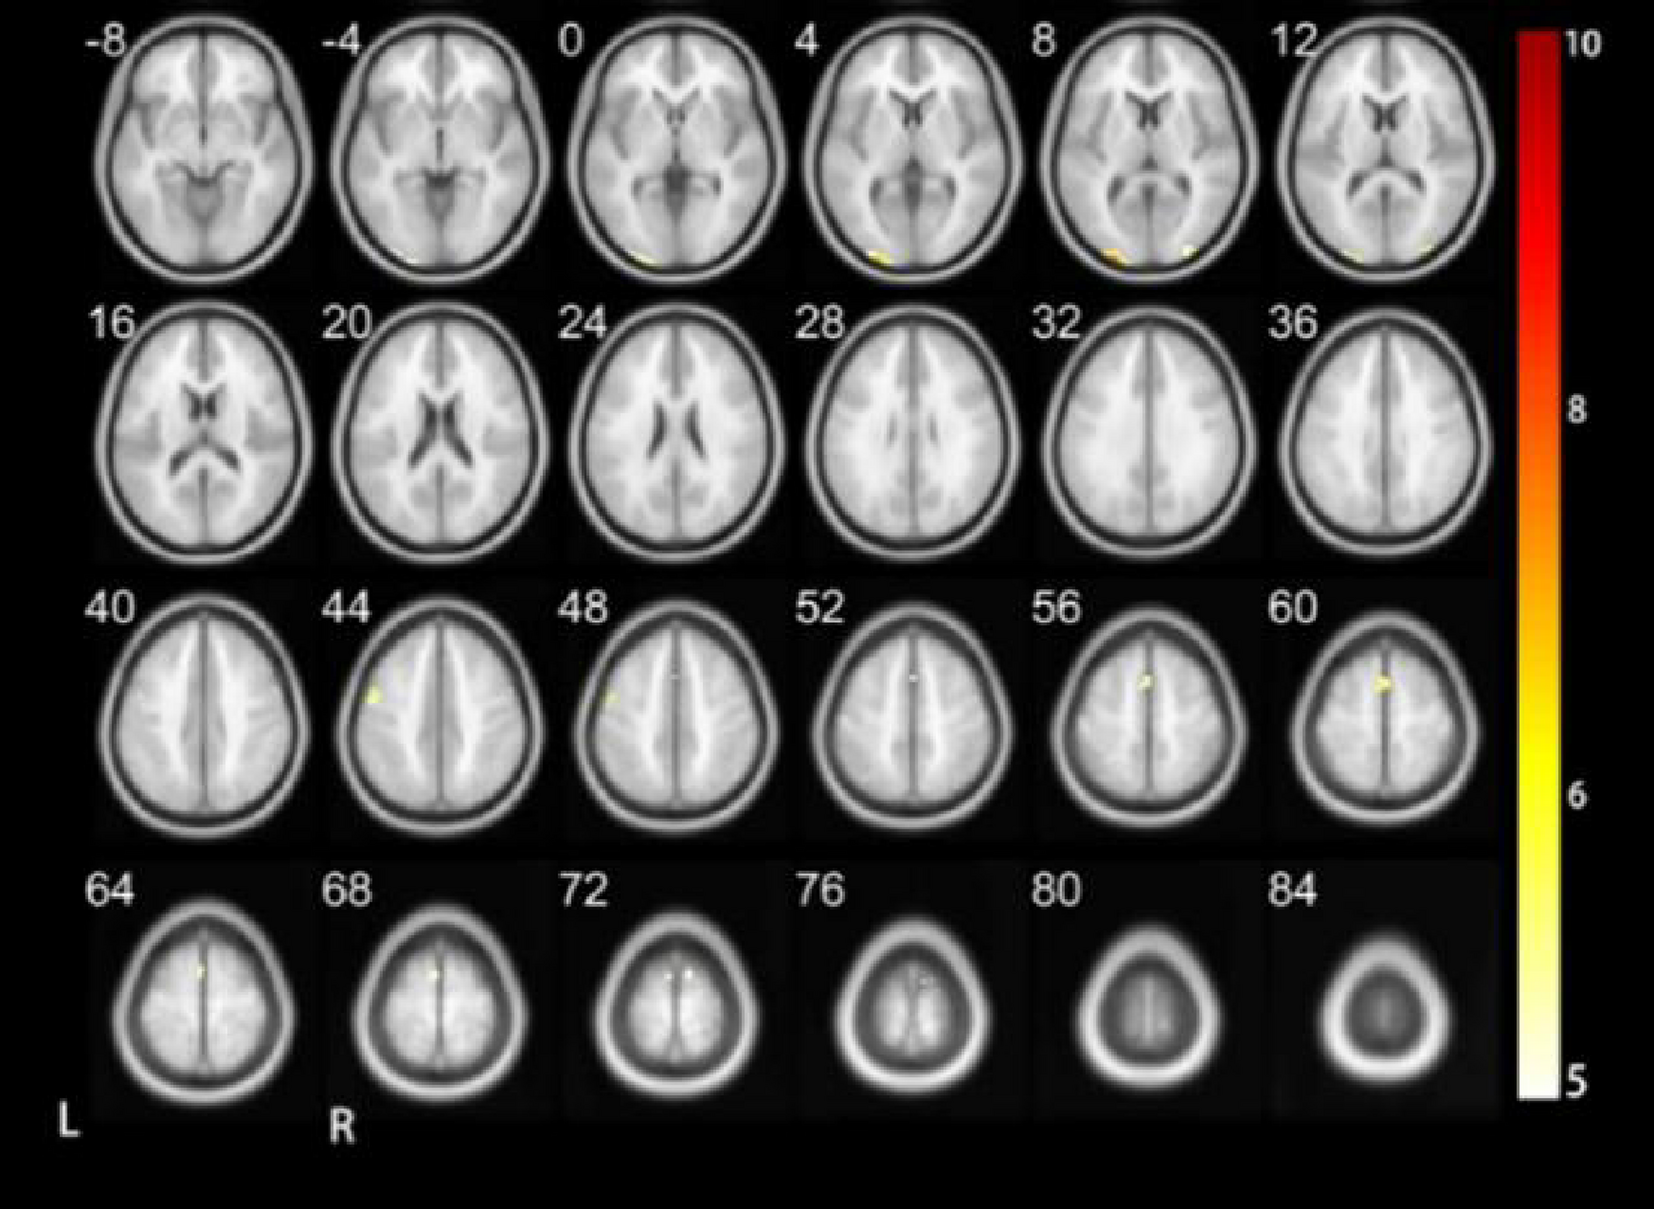

Fig. 4

Results of DC when performing the tone 2 task.